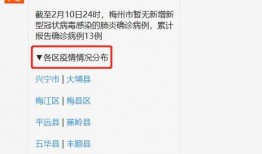

梅州最新爆料消息今天疫情,揭秘病毒传播轨迹与防控措施”

你知道吗?最近梅州又有了新的疫情动态,这可是个大新闻呢!今天,我们就来聊聊这个话题,看看梅州疫情的最新情况。梅州疫情最新进展首先...